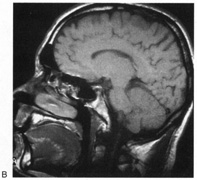

Fig. 10. Striate quadrantanopia. A. A 68-year-old woman with a stroke 3 years previously, causing left inferior quadrantanopia. B. MRI shows infarct of the superior bank of the right calcarine cortex.

Selective lesions can also occur along the anterior-posterior extent of striate cortex. A lesion of the occipital pole alone causes homonymous central hemiscotomata (Fig. 11).44,50 This can occur with watershed infarcts during systemic hypoperfusion. Slightly more anterior lesions in the middle zone of striate cortex cause homonymous peripheral scotomata (Fig. 12). The highly congruent, homonymous nature of these defects and their restriction to one hemifield differentiate these from ocular causes of central or paracentral visual loss. Lesions with such small field defects can be missed on CT.43 MRI with coronal sections through the occipital lobes should be performed, although even this may miss small lesions, particularly at the occipital pole.